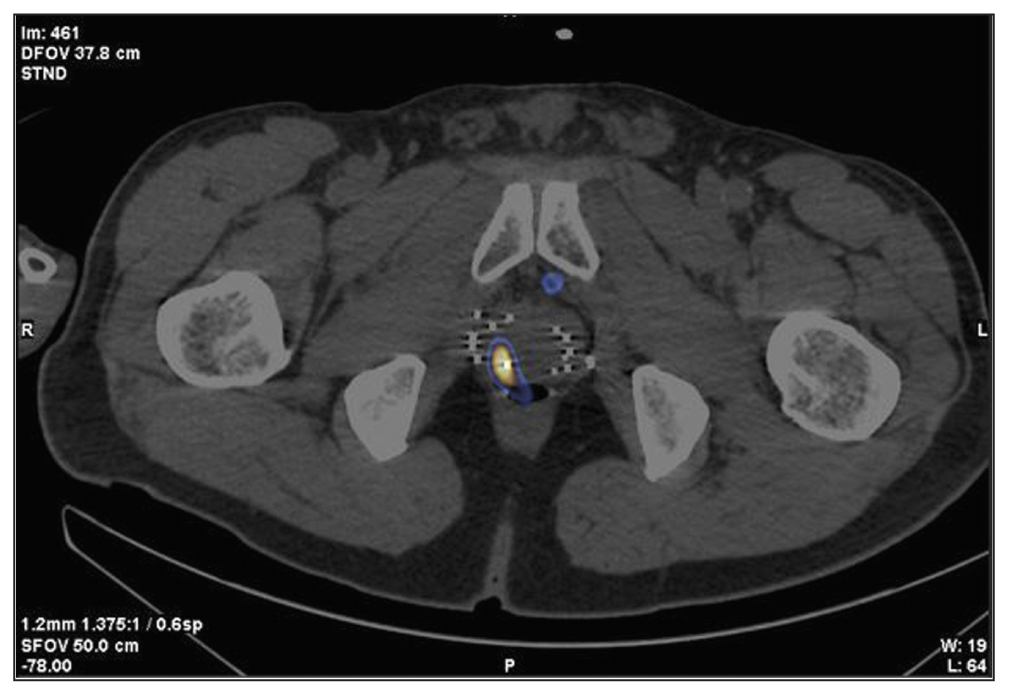

Patient F., 68 years old, was admitted with prostate cancer, T3a, which had spread to the prostate gland capsule. In 2013, 125I sources were implanted into the prostate tissue and the extracapsular area. PSA has increased since the end of 2020. SPECT/CT was performed using 99mTc-HYNIC-PSMA due to an increased PSA level of 0.95–2.8 ng/mL after the previous treatment (Figure 5). SPECT/CT revealed a 15-mm3 site of tumor tropic RP accumulation, which was biopsied under the CT guide. A histological diagnosis was prostate adenocarcinoma, Gleason 6 (3 + 3). Dosimetry planning for low-dose brachytherapy was performed using SPECT/CT. On November 03, 2021, 125I microsources were re-implanted according to topometric markings to implement the dosimetry plan. The PSA level was 0.05 ng/mL during the follow-up examination (January 23, 2023).

Fig. 5. Patient F., 68 years old, SPECT/CT with 99mTc-HYNIC-PSMA: Sites of radiopharmaceutical accumulation at the border of the central zone and the posterolateral part of the peripheral zone on the right side at the level of the base of the right prostate lobe. The scan visualizes multiple rods in the prostate gland, implanted during previous brachytherapy.

In this case, SPECT/CT with 99mTc-HYNIC-PSMA allowed for a precision biopsy, which confirmed the local recurrence of prostate cancer and subsequently enabled brachytherapy to be repeated (salvage) under the CT guide.